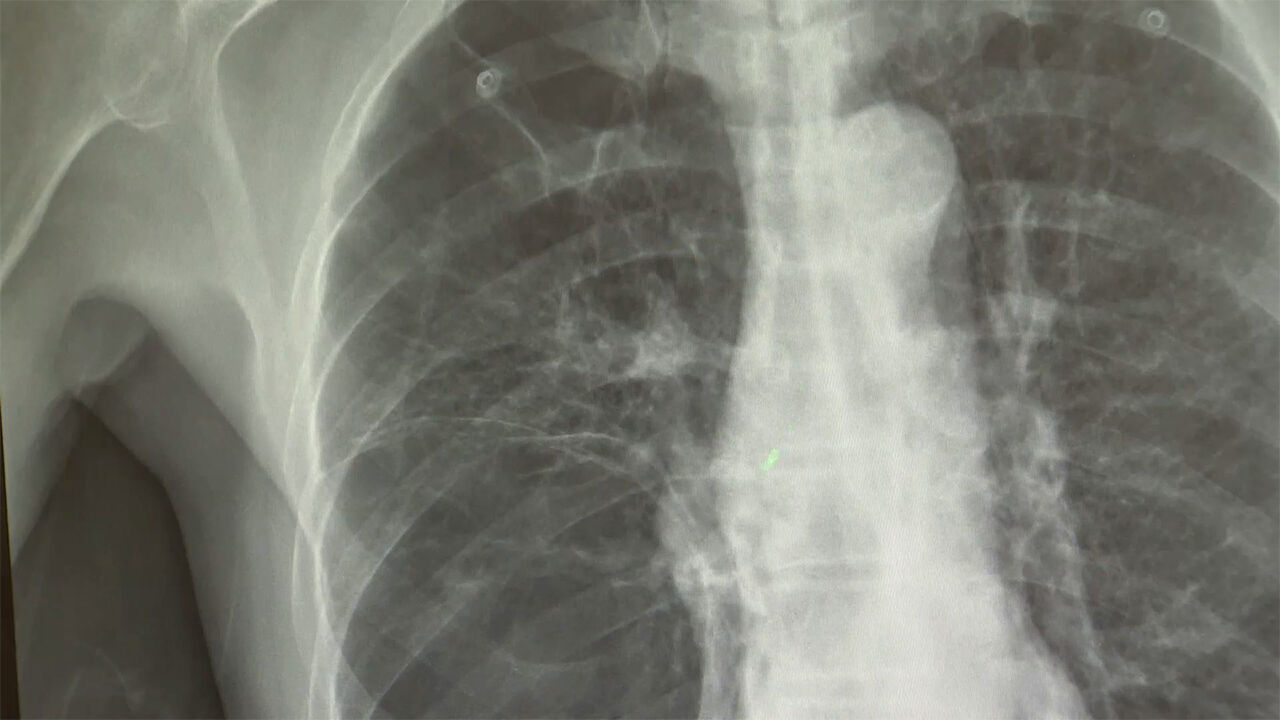

▲ 폐암 X-RAY

담배를 전혀 피우지 않더라도 만성 폐 질환을 앓았던 병력이 있다면 폐암 발병 위험이 3배 가까이 높아진다는 연구 결과가 나왔습니다.

분석 결과 폐결핵 등 폐 관련 질환 병력이 있는 비흡연자는 일반인보다 폐암 위험이 2.91배 높았으며, 특히 만성폐쇄성폐질환인 COPD 환자의 경우 위험도가 7.26배까지 치솟았습니다.